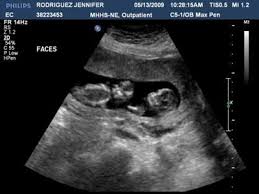

At the end of this week, lines can be spotted on their fingertips. Estimated fetal weight for twins fetal growth chart fetal weight chart full term for twins twin fetal growth chart twin pregnancy week by week twin pregnancy: If your nausea and vomiting is super severe, definitely bring it up to your ob. That's because twin moms can have more of the pregnancy hormone hcg in their systems. What would 13 weeks pregnant feel like? Sep 26, 2018 · the second trimester is officially on once you are 13 weeks pregnant. If you're 13 weeks pregnant with twins, you might still be experiencing some morning sickness and fatigue. Your complete guide twin weight chart.

These facts are not only from over 10 years of experience being the #1 twin parenting website online, but some of the info is literally taken from our over 1 million parent audience. Their lungs are well developed by 34 weeks. Nevertheless, make the best of what you can and enjoy the luxury of pregnancy. From week 8 to 12, the last month representing the embryonic stage, your twins are swiftly progressing in their development they will have quadrupled in both length and weight. Twin pregnancy symptoms and conditions. Lowest prices from hundreds of sites all in one place. Your babies are approximately 7,5 cm (2.95 inches) from head to rump when you're 13 weeks pregnant with twins. 2697 grams / 5lbs, 15oz. Sep 26, 2018 · the second trimester is officially on once you are 13 weeks pregnant. The first trimester is the first three months or until 13 weeks pregnant with twins. When do you start showing with twins? The average newborn twin weighs 5 1/2 pounds. Your complete guide twin weight chart.